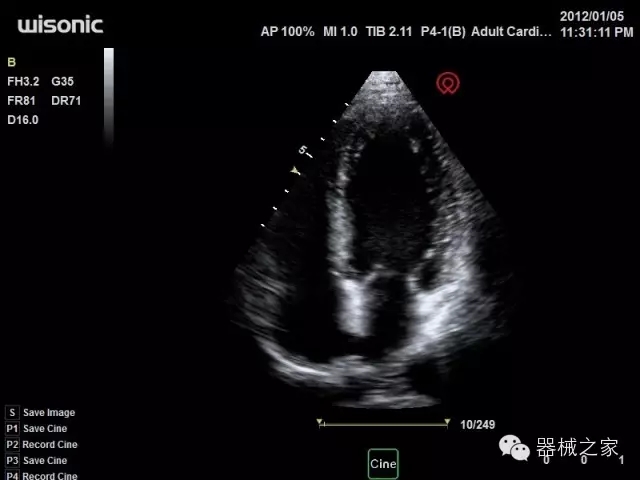

臨床圖片賞析

產(chǎn)品特點(diǎn)

·全球目前唯一一款配備主機(jī)雙探頭接口,整機(jī)重量(含電池)在5公斤以內(nèi)的便攜式彩超;

·一款互聯(lián)網(wǎng)彩超,只要有手機(jī)信號(hào)的地方就可以非常方便地實(shí)現(xiàn)遠(yuǎn)程會(huì)診和病案調(diào)取;

·鎂鋁合金外殼,堅(jiān)固可靠耐用;

·獨(dú)有的HoloTM PW 實(shí)時(shí)3取樣門(mén)PW成像技術(shù),精確進(jìn)行血管診斷;

·一鍵優(yōu)化B、Color、PW,Auto Doppler自動(dòng)識(shí)別血管位置、偏轉(zhuǎn)角度等,提高工作效率;

·30°超廣角精細(xì)偏轉(zhuǎn)成像技術(shù),更優(yōu)異的頻譜圖像;

·W+智能搜索引擎,快速尋找圖像;

·SSD、USB3.0保障開(kāi)機(jī)快,導(dǎo)出圖像更快,減少等待時(shí)間;

·WIFI、網(wǎng)口、3G,多重聯(lián)網(wǎng)方式,全天候保障云端備份,不再擔(dān)心圖像丟失;